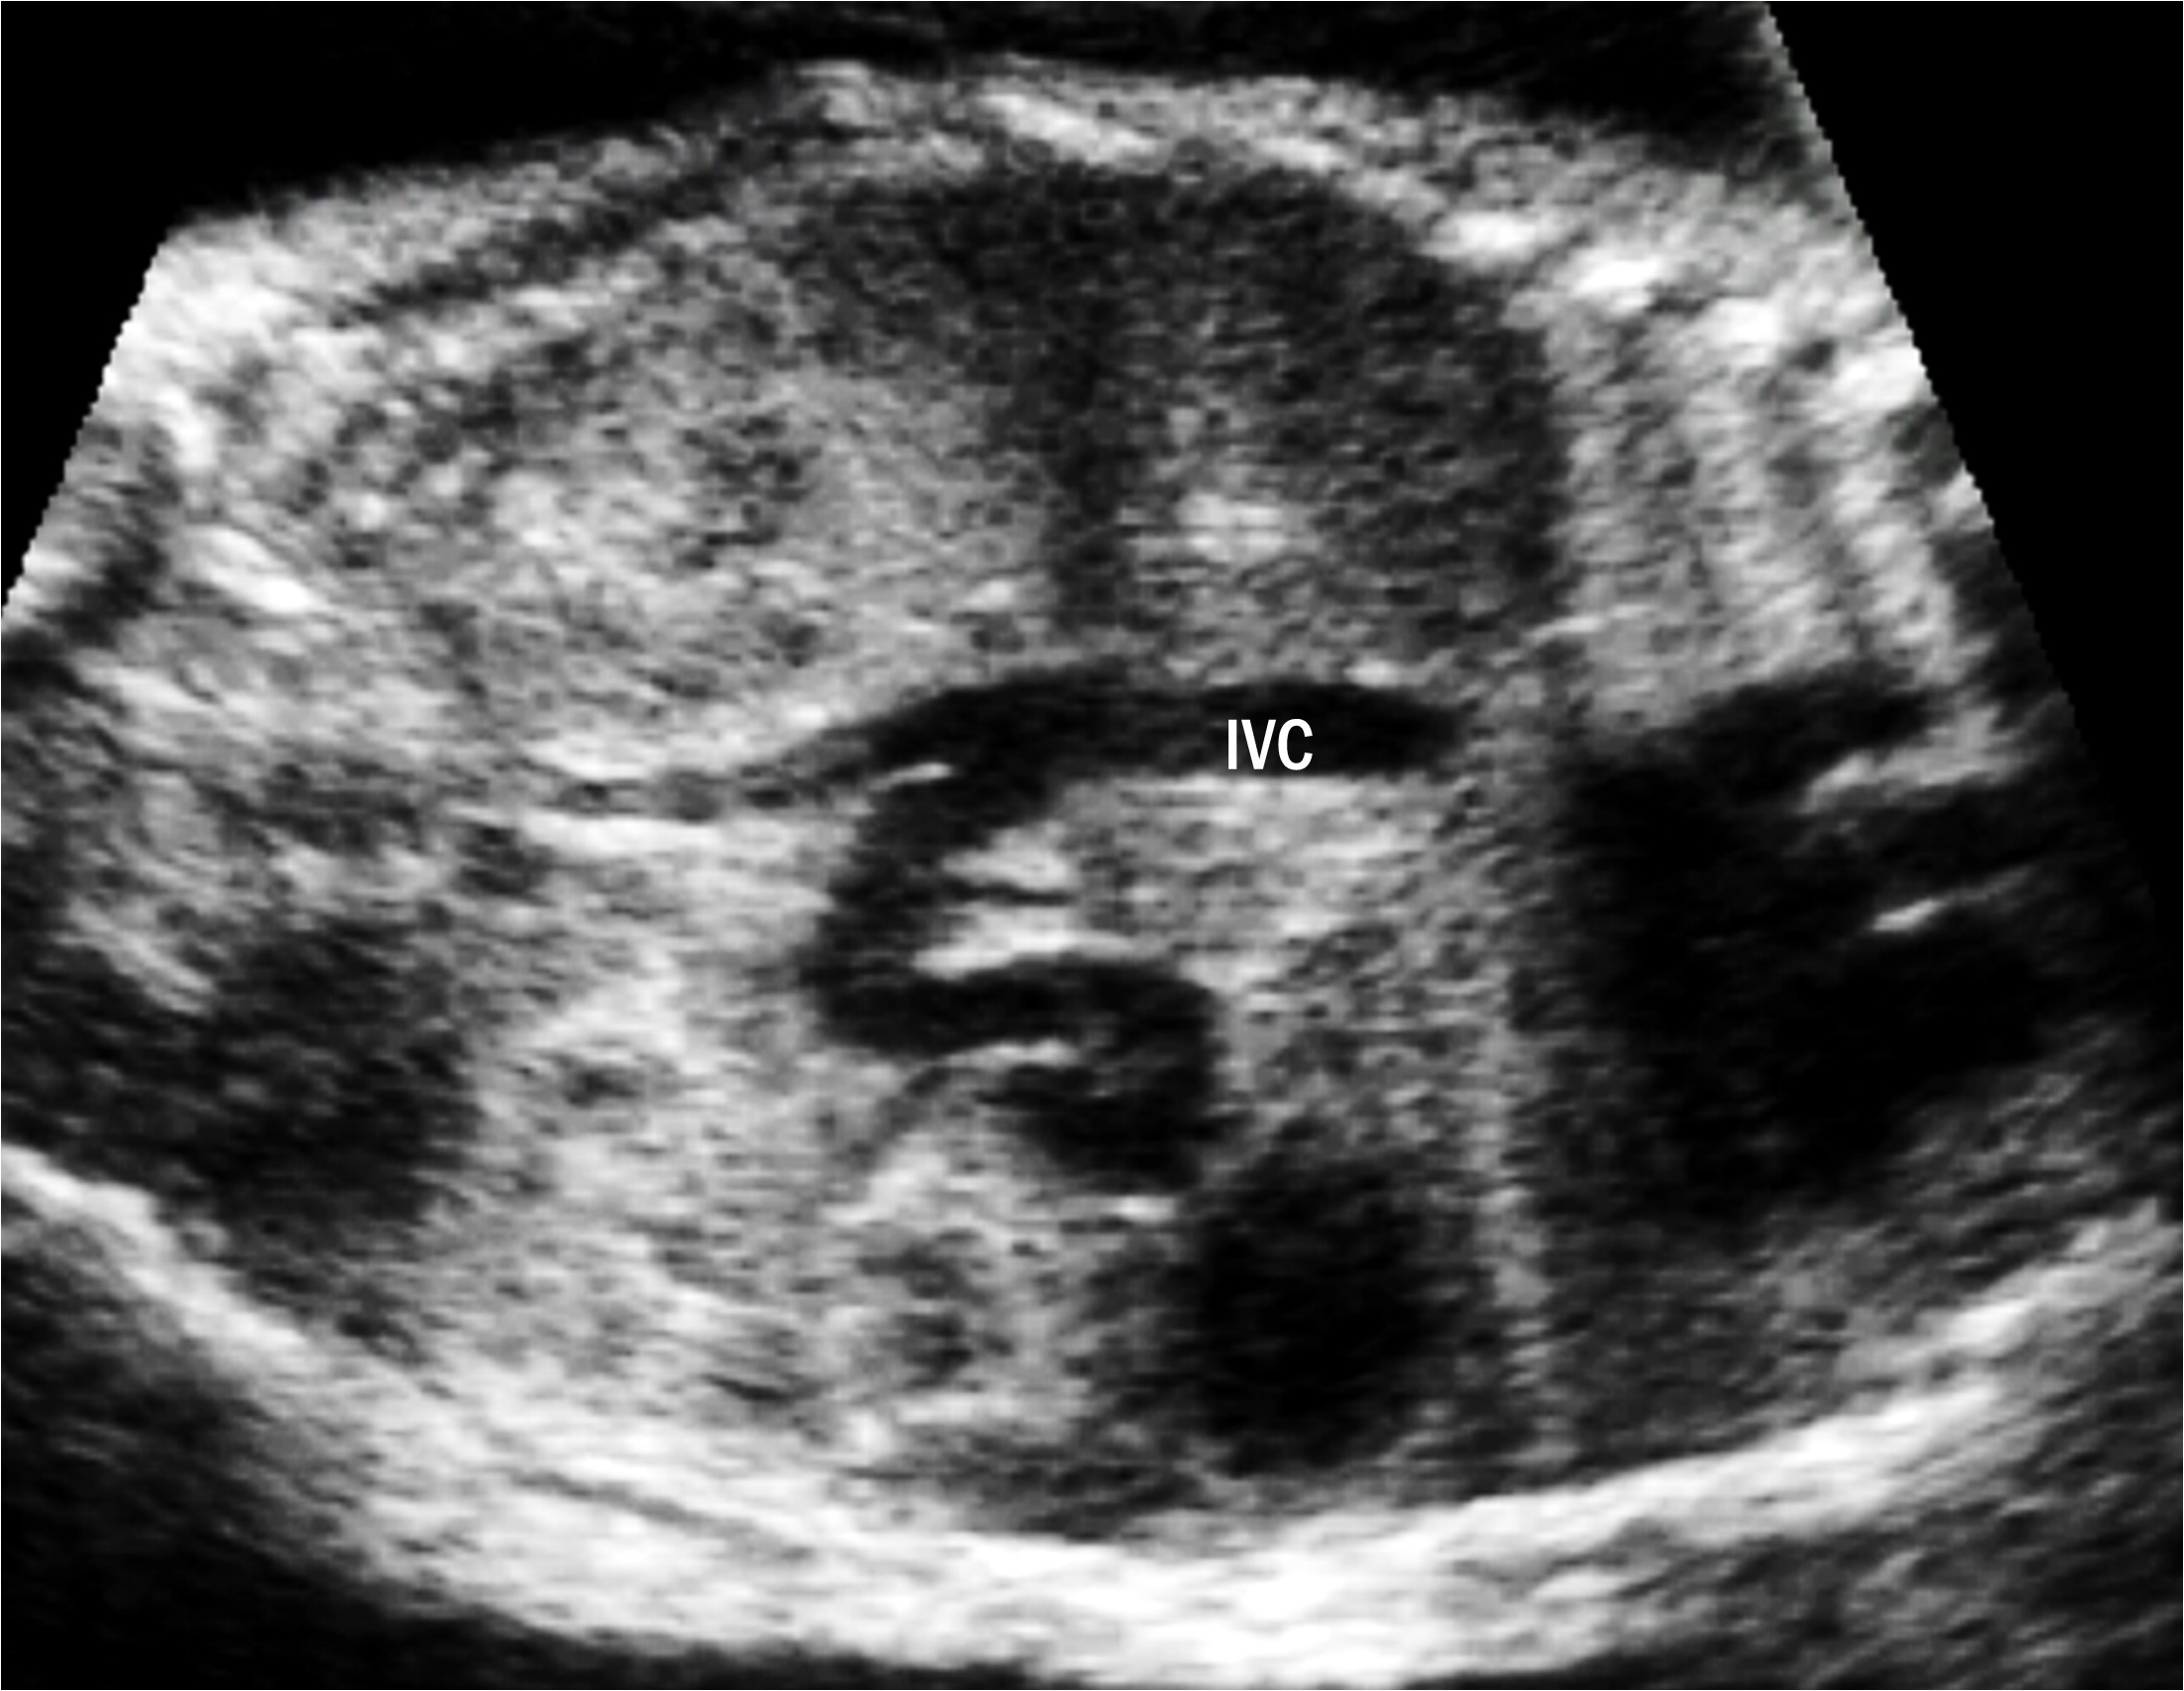

One case of type IIIb UPSVS was identified (case 14). Prenatal ultrasonography revealed an abnormal tortuous vessel communicating between the PV and IVC (Fig. 5). Due to this shunting flow, the IVC became enlarged; otherwise, the umbilical-portal-DV complex was intact. The fetus was below the 3rd percentile and had both cardiac and extra-cardiac anomalies. Additionally, the karyotype results showed an unbalanced (X;22) translocation. The neonate suffered from bronchial stenosis and died due to pulmonary hypertension and heart failure at the age of three months.

Fig. 5.Extrahepatic portal-systemic shunt in case 14. The portal vein (PV) is connected to the inferior vena cava (IVC).